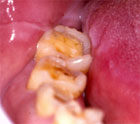

Bajo grado de trauma intrínseco, pero que al igual que el anterior, perpetuado en el tiempo, puede producir disfunción articular. En este apartado nos encontraríamos el apretamiento dentario. BRUXISMO (Fig. 9, 10, 11).

Fig.9 Atricción Dentaria por Bruxismo

Fig. 10 Atricción Severa por Bruxismo

El mantener y repetir cargas adversas sobre el sistema masticatorio durante una parafunción oral como el bruxismo, puede tener una relación directa con la disfunción de la ATM.

Manfredini y col. (29) investigaron la prevalencia en 212 pacientes diagnosticados de bruxismo y con alteraciones articulares y 77 sujetos bruxistas sin alteraciones de la ATM. Existe una evidente asociación entre el Bruxismo y los Trastornos Temporomandibulares (P<0,05). Los cuadros más frecuentes asociados con bruxismo son: Dolor Miofascial y Desplazamiento Discal, el 87,5%. El 73,3% presentaba Dolor Miofascial, Desplazamiento Discal y otras alteraciones articulares. El 68,9% Dolor Miofascial únicamente.

Fig. 11 Dentina Expuesta por Bruxismo

Es decir, el bruxismo tiene una relación más directa con alteraciones musculares que con las puramente articulares.